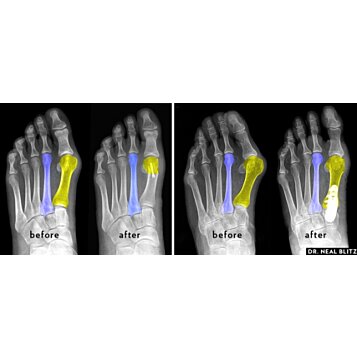

- Dlaha na korekciu vykriveného palca, výrastkov a pľuzgierov halux - biela 2ks2,60 €VypredanéMJ6106